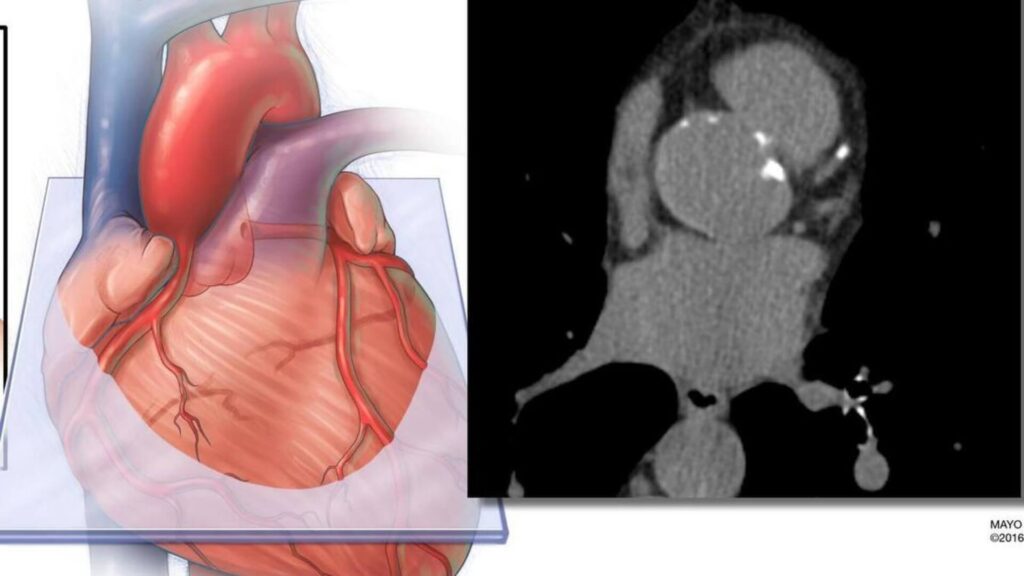

El estudio realizó un seguimiento de casi 12.000 adultos durante aproximadamente 16 años. Los investigadores aplicaron IA a las tomografías estándar de calcio en arterias coronarias de los participantes para medir la grasa que rodea el corazón. Compararon el valor predictivo de esta medición, tanto de forma independiente como en combinación, con dos enfoques estándar de evaluación del riesgo: la ecuación PREVENT de la American Heart Association, que incorpora factores tradicionales como edad, sexo, presión arterial, colesterol, diabetes y otras variables, y la puntuación de calcio en arterias coronarias, que cuantifica la placa calcificada en las arterias coronarias.

La cuantificación del calcio en arterias coronarias se utiliza ampliamente para evaluar el riesgo cardiovascular. Este estudio demuestra que puede extraerse información adicional de la misma exploración sin necesidad de pruebas adicionales ni costes añadidos.